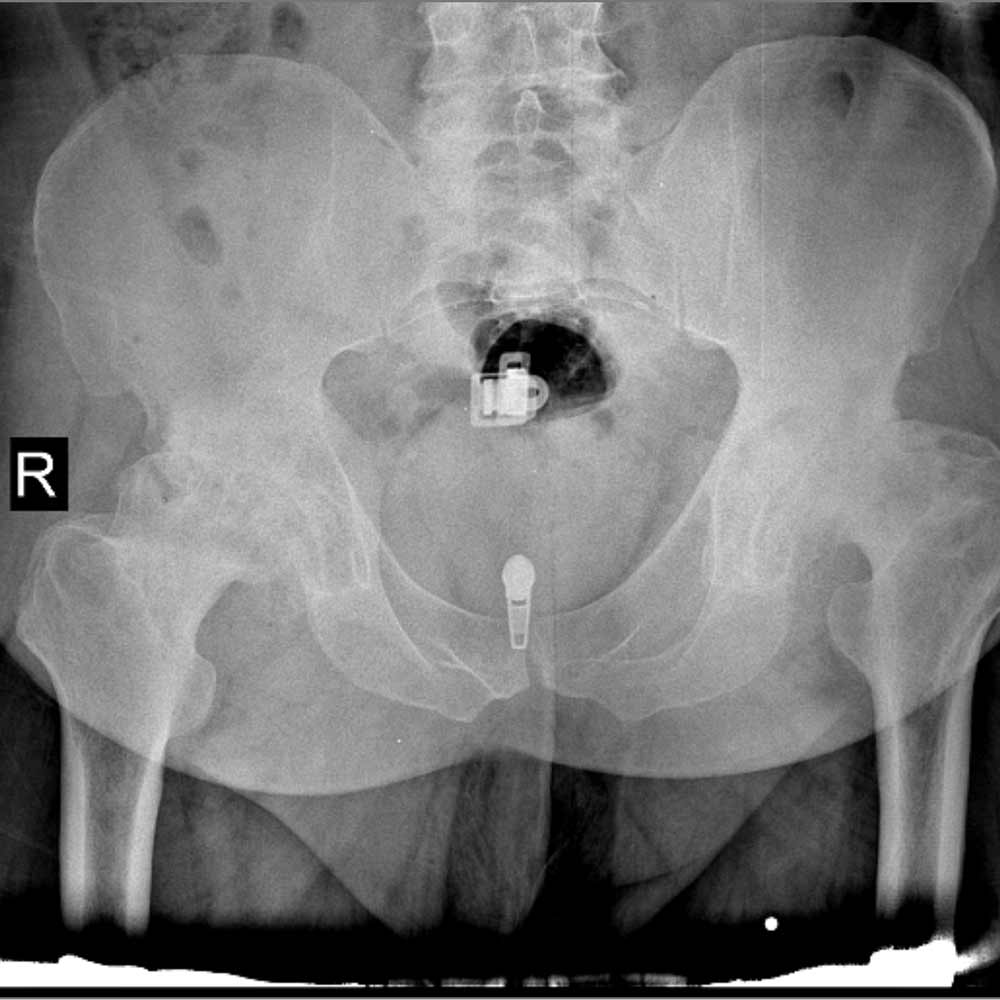

در نهایت، روش های تصویر برداری مثل رادیوگرافی به تشخیص بیماری کمک میکند. مهمترین روش تصویربرداری برای تشخیص ساییدگی لگن رادیوگرافی ساده است. تشخیص این بیماری نیاز به سی تی اسکن یا ام ار آی ندارد.

در تصویر رادیوگرافی از مفصل، چون غضروف نازک شده است فاصله مفصلی یا فاصله بین دو استخوانی که مفصل را تشکیل داده اند و در حد چند میلیمتر است کاهش پیدا میکند و در کناره های استخوان های تشکیل دهنده مفصل استخوان اضافی دیده میشود.

همچنین ممکن است کیست های استخوانی در بالای استابولوم یا در سر استخوان ران دیده شود.

در زیر تصاویری از عکس ساییدگی لگن در چند بیمار را میبینید. با کلیک بر روی هر کدام تصویر بزرگتری از آن را خواهید دید.